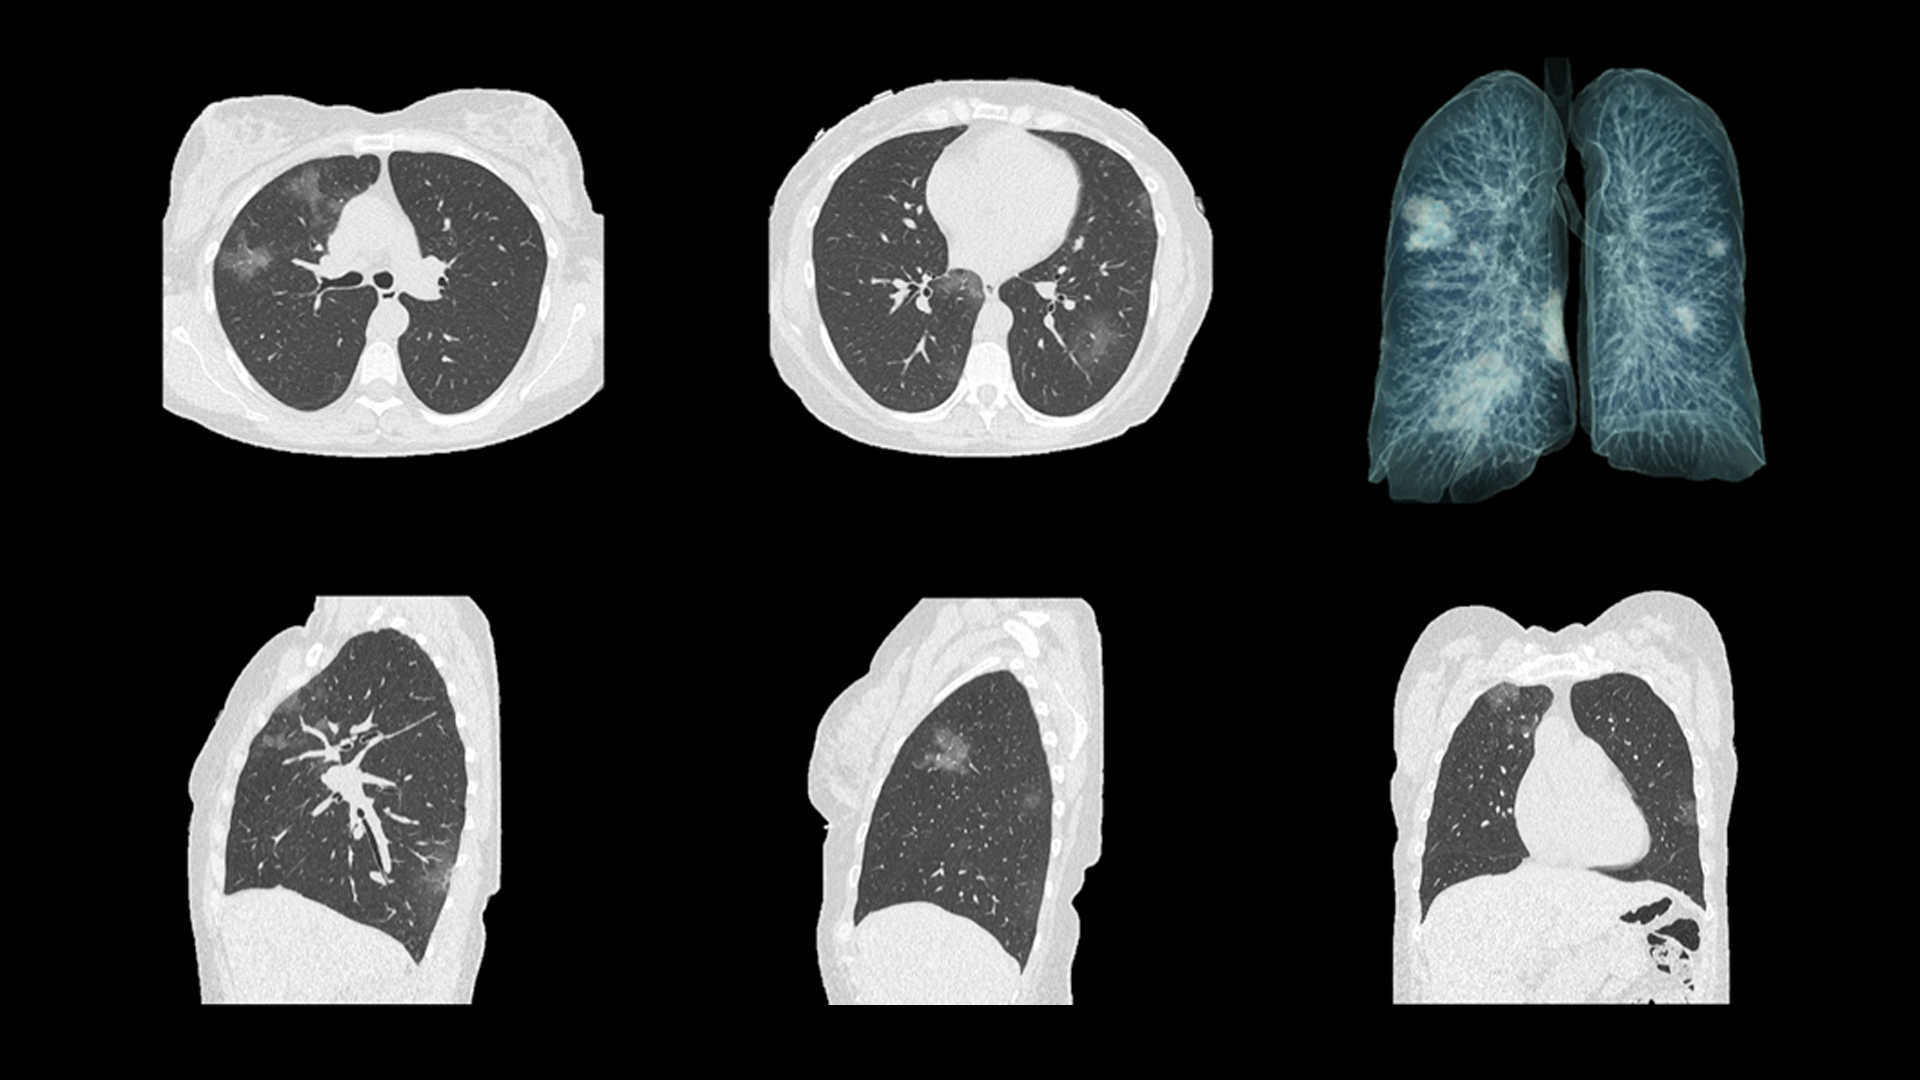

CT imaging helps to evaluate COVID-19 patients and survey their progression

Stato dell’arte sull’impiego della diagnostica per immagini per COVID-19.